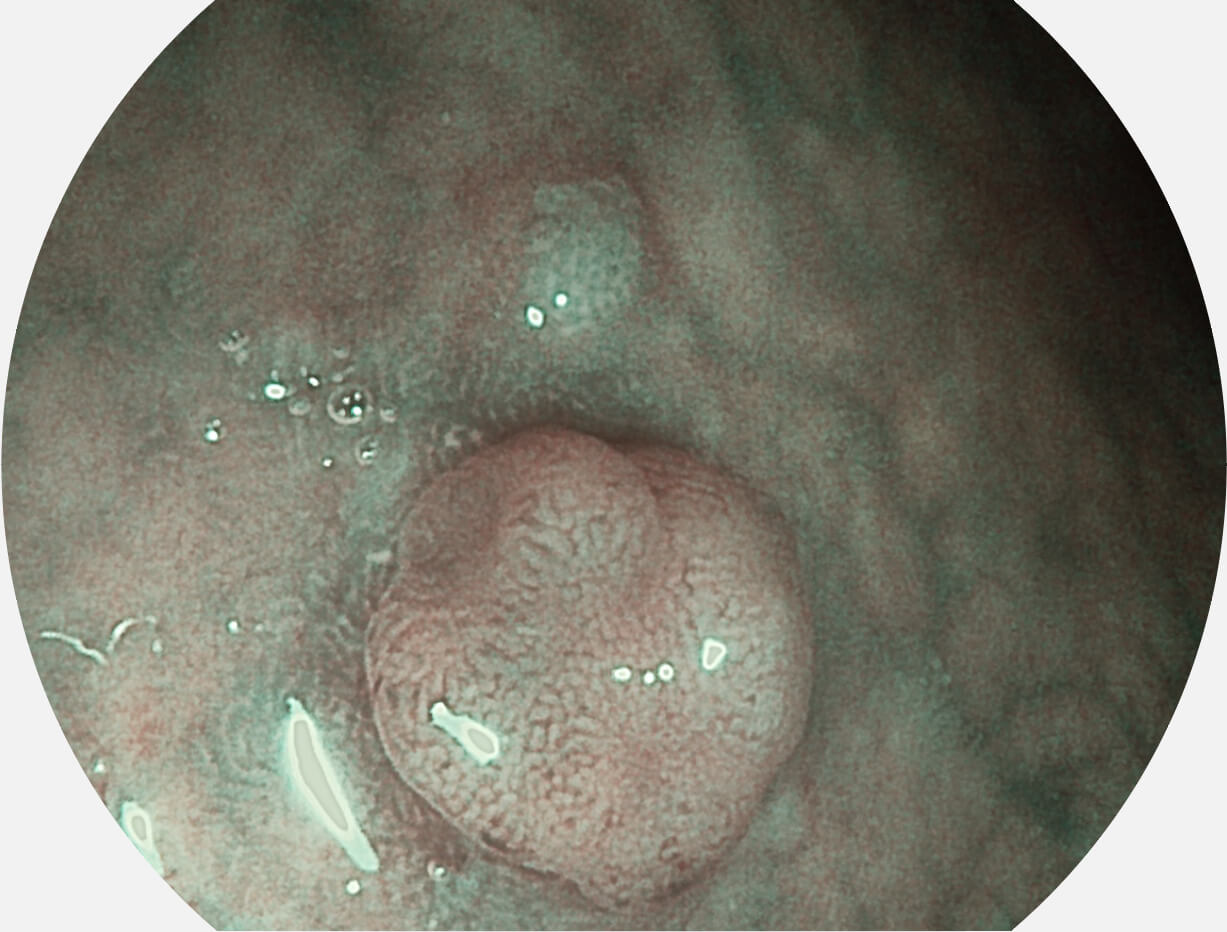

白光图像

SFI图像

Spectral Focused lmaging, SFI

图像具有高亮度、高黏膜血管颜色对比度的特点,且不改变粘液、食物残渣、粪便的基本颜色,可在中远景下进行观察,助力消化道早期疾病的诊断。